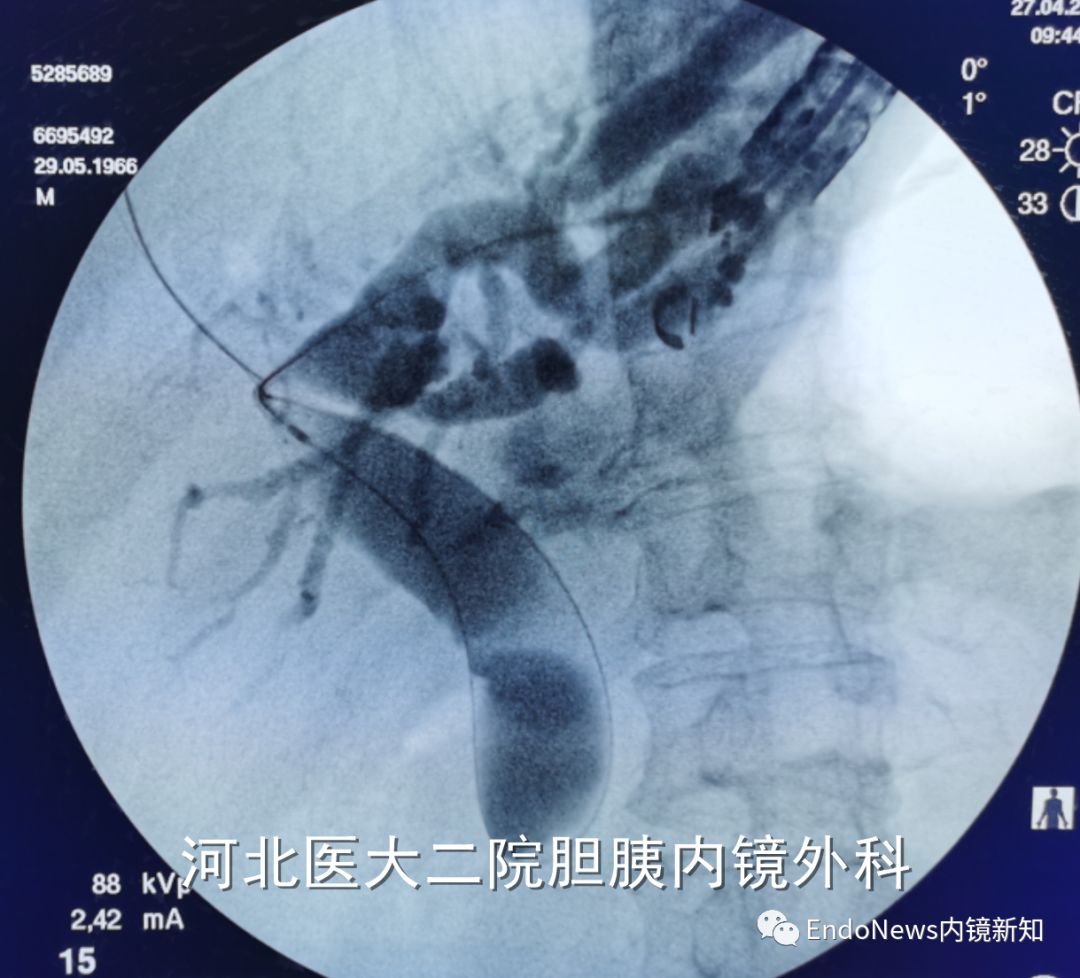

行经十二指肠胆管穿刺(CDS)时一般不需要考虑以上问题,但如因某些特殊原因涉及到会师操作时可能涉及到导丝自胆总管上游朝向下游的超选。一般情况下,CDS的时候穿刺针的方向是朝向肝内的,比如下图:

如果这个时候放支架行CDS就可以结束手术了,如果需要做顺行或者会师,就需要使导丝返折180°朝向胆管下游方向穿出十二指肠乳头。

也有一些时候穿刺后导丝方向本身就是朝向胆总管下游方向的,比如下面两个病例: